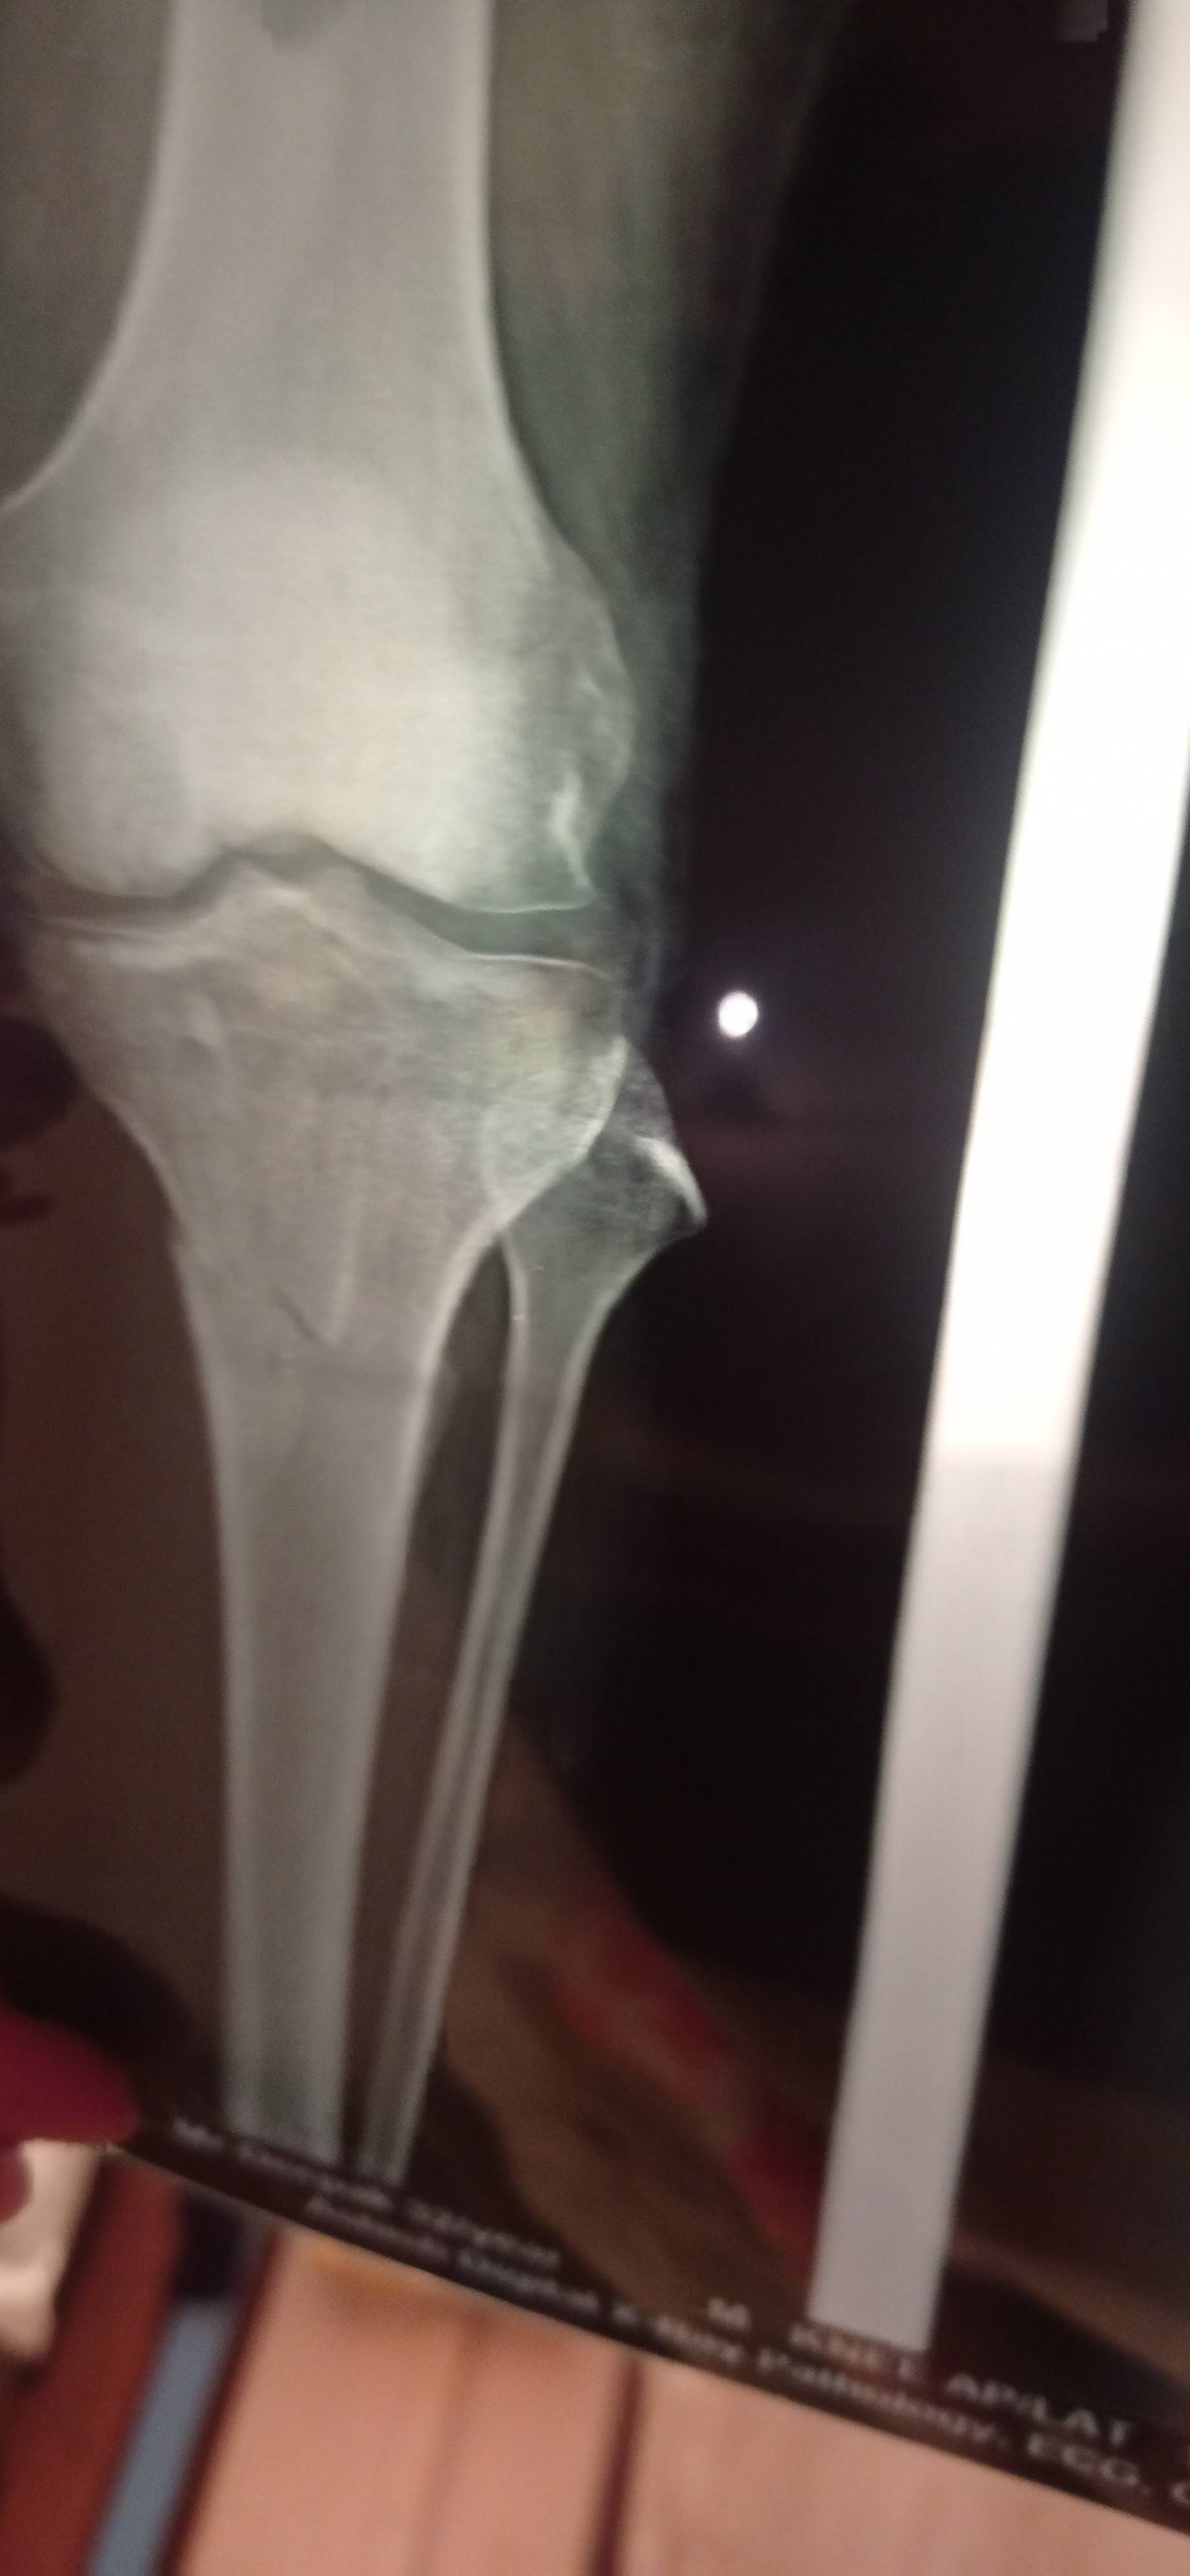

Sir mere per me 2 month pahale fracture hua tha isme mujhe operation karana padega y plaster s hi sahi ho jayega